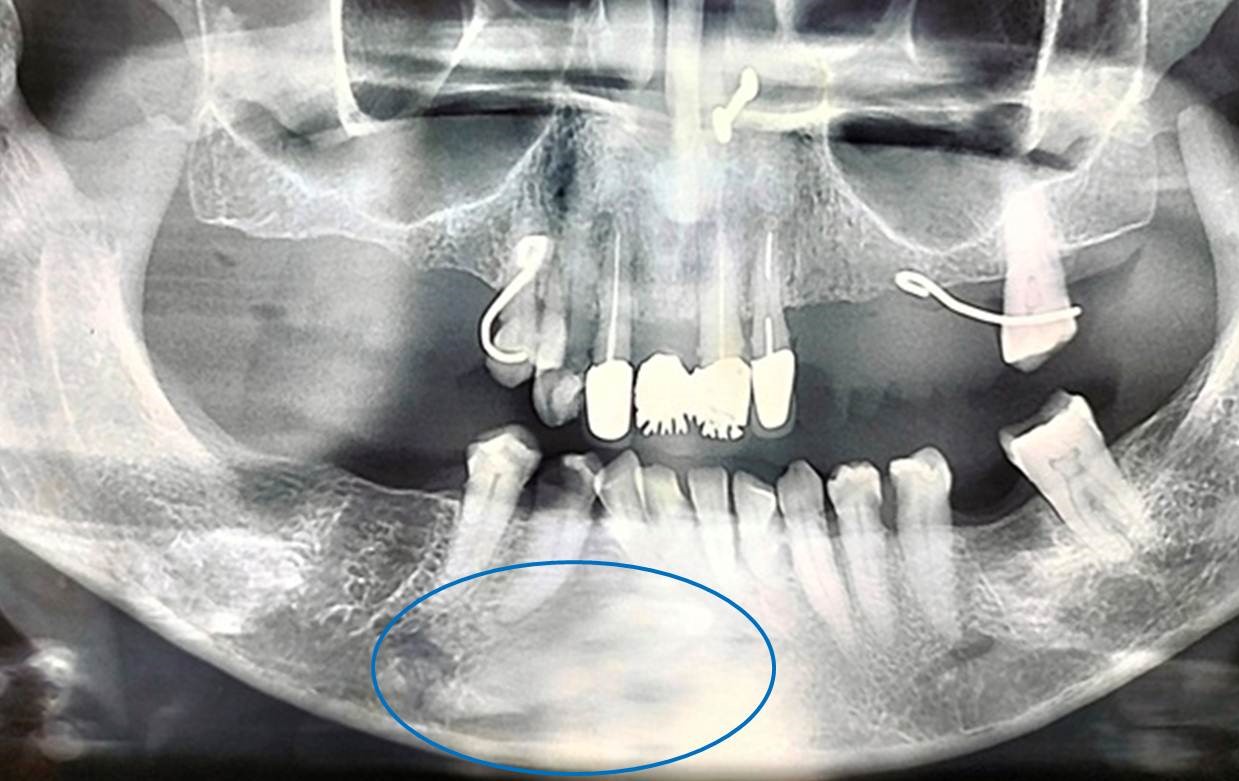

A 56 year female patient reported a private dental office wishing to replace her many missing teeth. Patient appeared moderately built and nourished with no signs and symptoms of any systemic or metabolic disorder. On intraoral examination, only maxillary anterior teeth including central,lateral incisors, canine, first premolar on right side, central, lateral incisors, canine and only second molar was present on the left side. In the mandibular arch, on the left side,central lateral incisors, canine, first and second premolars and second molars were present. On the right side only central,lateral incisor and both premolars were present.Mandibular right canine appeared to be missing. Patient’s oral health was poor with severe periodontal problem. On further examination of the oral cavity patient also exhibited an old broken removable partial denture along with some fixed prosthetic components. Patient had lost many permanent teeth due to periodontal problem, as a result the occlusion was not proper. An orthopantograph radiograph was taken which showed an impacted mandibular right canine(Figure 1). The canine was placed slightly angulated and deviated towards the occlusal level. The crown of the canine was facing towards midline and the root opposite side.About one third of the crown of the impacted canine crossed the midline. On left side the canine erupted in normal place in vertical position. Based on literature search the case was diagnosed as transmigration and belonged to type I category. As tooth was in asymptomatic condition no treatment was carried out. Addressing patient chief complaint a removable prosthesis was planned.

The diagnosis of transmigration involves clinical examination and radiographic assessment [15,16]. The clinical examination includes visual inspection and palpation of the affected area to detect any abnormality in the position,shape, or mobility of the tooth. However, the radiographic assessment is considered the gold standard for the diagnosis of transmigration such as involves taking a panoramic radiograph [17].

The panoramic radiograph helps to confirm the diagnosis of transmigration by showing the position of the tooth relative to the midline and adjacent teeth, the degree of inclination, and the extent of migration [18]. In some cases,cone-beam computed tomography (CBCT) may also be used to obtain a more detailed image of the transmigrated tooth and its surrounding structures [19]. Furthermore, it is important to differentiate transmigration from other dental anomalies, such as impacted teeth, odontomas, and dentigerous cysts, which may have similar clinical and radiographic features [20]. Therefore, a thorough examination and analysis of the radiographic images are essential for an accurate diagnosis and treatment planning. Sometimes it is observed with other dental anomalies. Nagaveni et al in 2011 reported concomitant occurrence of canine transmigration and symmetrical agenesis of mandibular both central incisors [21]. Later in 2012, the same author published an unusual occurrence of a combination of dental anomalies like mandibular canine transmigration (type I), taurodontism in permanent mandibular molars, congenital agenesis of 14 numbers of permanent teeth excluding third molars, canine impaction, primary molars with pyramidal roots, midline diastema and generalized microdontia in an apparently normal 13-year-old Indian girl [22].